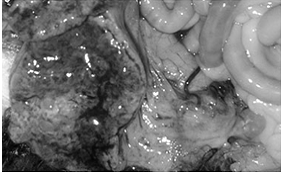

Причина: Типичная пиометра предположительно вызывается первичными инфекционными процессами. Примерно в конце эструса или начале проэструса бактерии поднимаются через открытую шейку матки в матку и вызывают воспаление. Повышение уровня прогестерона вызывает закрытие матки и одновременно уменьшает устойчивость эндометрия к бактериальным инфекциям. Количество бактерий в матке увеличивается, и возникает эндометрит с гиперсекрецией маточных желез. Постепенно матка наполняется гнойным секретом. Токсины из содержимого матки всасываются, и это приводит к токсемии. Острая фаза воспаления протекает клинически незаметно, фаза токсемии может проявляться различным образом. При анализе содержимого матки собак, страдающих пиометрой, обнаруживаются преимущественно неспецифические бактерии (главным образом, Е. coli, однако также и стафилококки, клебсиеллы, пастереллы и др, бактерии) (рис. 14a, 14b, 15).

Закрывается канал шейки матки. А железы эндометрия начинают интенсивно продуцировать секрет, который скапливается в полости матки. Если при этом содержимое матки имеет водянистый характер, то болезнь называют водянкой матки, или гидрометрой (рис. 17), если слизистый - миксометрой. При значительном скоплении микробов из слизистой оболочки в жидкость мигрируют в большом количестве лейкоциты. Это ведет к гнойному распаду задержавшихся в полости матки выделений, развивается пиометра (рис. 18а, 18b). Накопление гнойных масс в полости матки может быть настолько велико, что стенки органа не выдерживают внутреннего давления и разрываются. Происходит излияние гноя в брюшную полость, что приводит к диффузному перитониту. Прободение стенки матки может произойти и вследствие гнойного расплавления тканей.

Осложнения: В высшей степени редким осложнением при пиометре является гнойный перитонит, который может быть вызван спонтанным разрывом матки (рис. 14b), ятрогенным разрывом при пальпации или распространившимся через яйцевод заражением брюшной полости. Клинически эти случаи отличаются тяжелыми нарушениями общего состояния и наличием болезненной вздутости живота (рис. 19).

рис. 15. Увеличение матки в результате накопления гноя (пиометра). Операционный препарат.